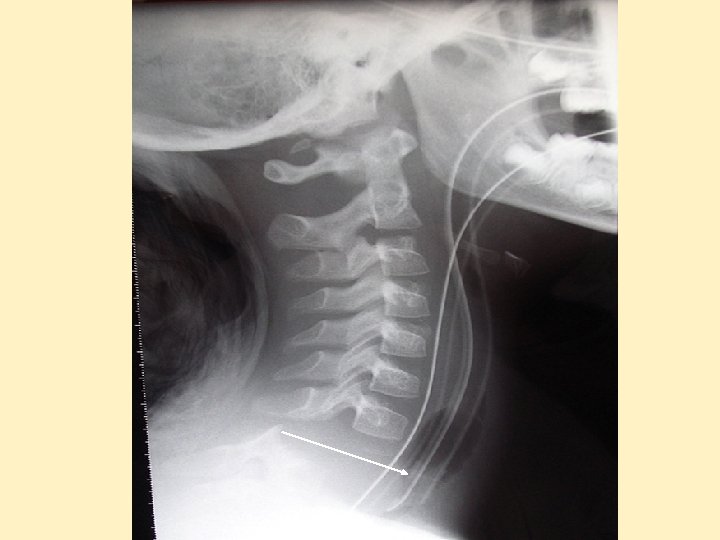

Lésions rachidiennes - Avant 8 ans: lésions cervicales, ACR réflexe ++ si > C 3 - Entre 8 et 12 ans: lésions dorso-lombaires ± abdomen - Adolescents = adultes - Rares mais mortalité propre très élevée, séquelles ++ - Lésions médullaires sans lésions radiologiques - Images pièges osseuses à connaître

Dislocation cervicale